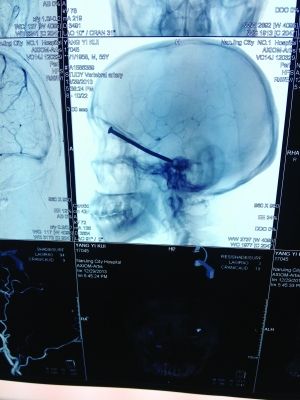

CT投影

CT投影結果,把大家嚇了一跳:楊先生腦子里居然有一根長釘,從眼眶一直“伸”到了接近后腦勺的位置!鐵釘細長略帶彎曲,長達8厘米。根據推測,鐵釘應該是從上眼眶的縫隙中飛入,一直插進腦顱中,末端還有一個小小凸出的釘帽。